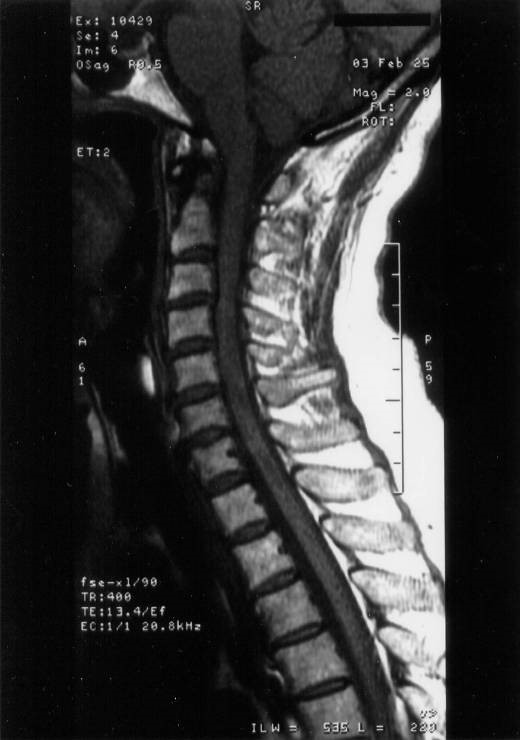

頸椎の変形と右側椎骨動脈奇形が発見されて、原因が判明(図8~12)。

図8

図9

図10

図11

図12